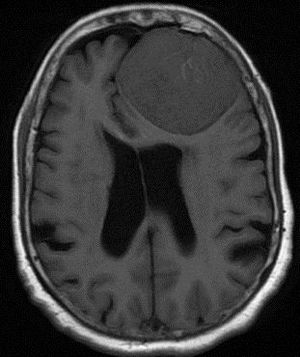

35-year-old female with prior history of breast carcinoma presented with frontal headaches.